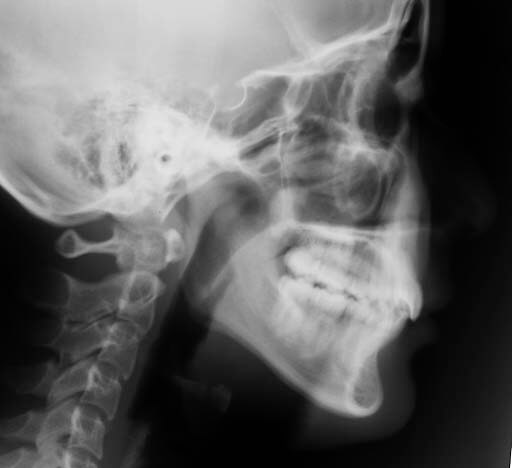

| セファロ所見 | 側方セファロ分析から、FH-U1 125°、L1-APOディスタンス -2.5mm、L1-APO アングル 15°と上顎前歯唇側傾斜、下顎前歯舌側傾斜が認めらた。 |